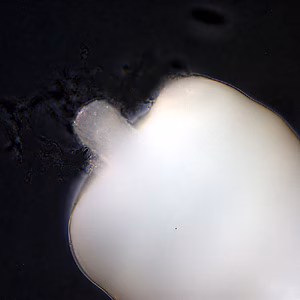

Adults of Macracanthorhynchus hirudinaceus.

Adults of Macracanthorhynchus hirudinaceus are large pseudocoelomates that vary in color from milky-white to pinkish to reddish. The body typically has a wrinkled appearance, giving the illusion of segmentation (pseudosegmentation). Adult females measure 18–65 cm long by 4–10 mm wide; adult males measure 5–10 cm long by 3–5 mm wide. The proboscis contains 5 or 6 rows of recurved hooks. Adults reside in the intestine of the definitive host, which is usually a pig. In humans, the worms seldom mature and when they do, rarely produce eggs.